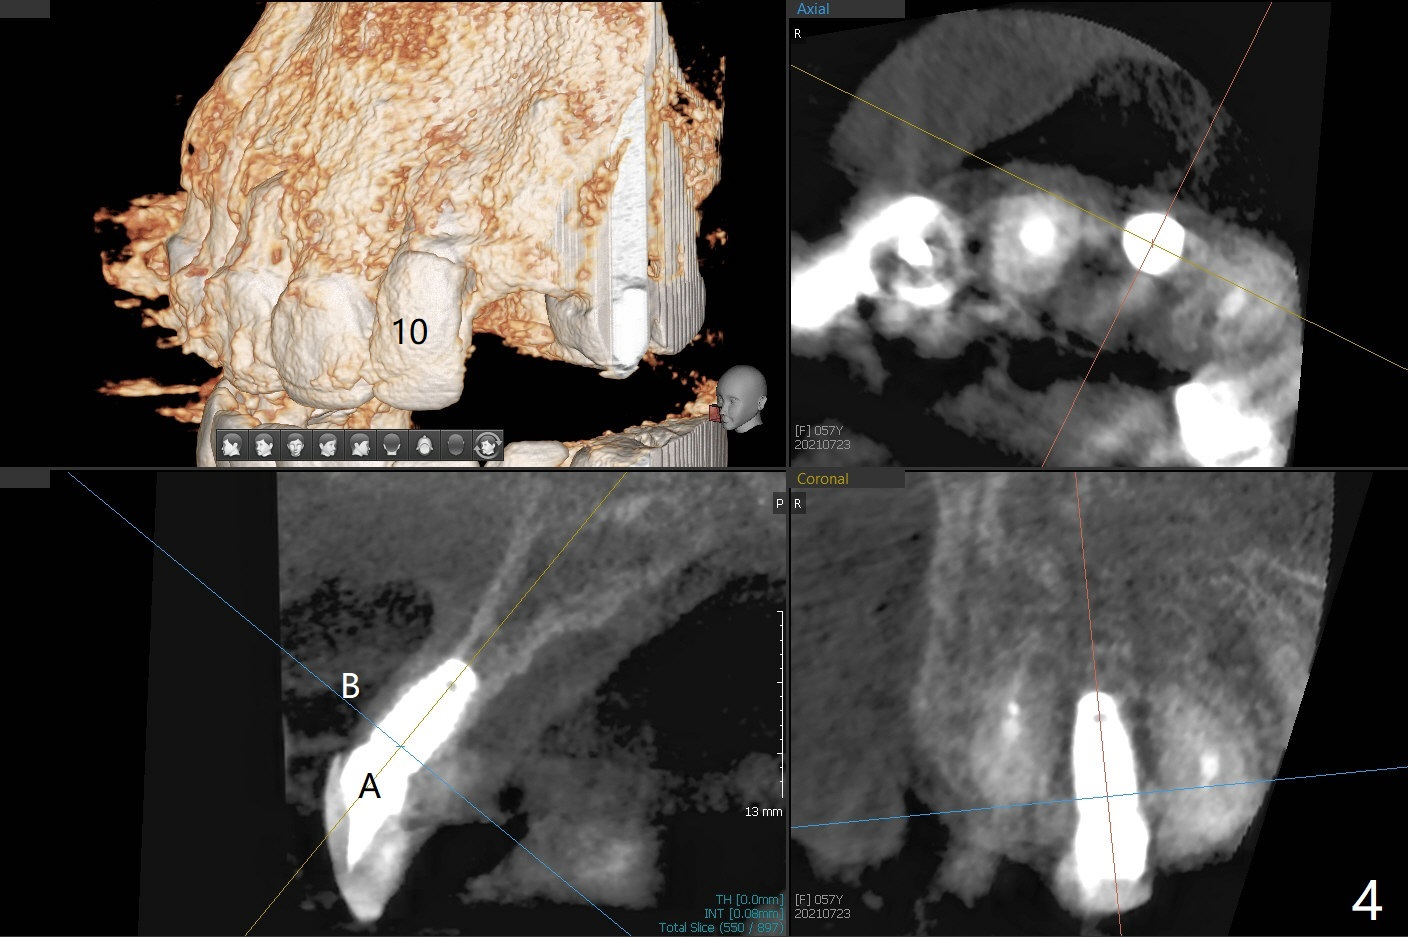

A 57-year-old woman presented to office with dislodged canine crown 10 months earlier (Fig.1). It was cemented. It dislodged again lately. She decides to have an implant and mentions looseness of the implant crown of the lateral incisor. Gingival recession is severe at #10 (Fig.2), while #11 has subgingival fracture (Fig.3). The recession is related to suboptimal angulation and buccal placement of the fixture (Fig.4), while the implant at #11 will be narrow and be placed with sufficient remaining buccal and palatal bone (Fig.5). Socket shield may be done. Prepare gingival retractors. In fact socket shield is not done because of caries in the root stump.